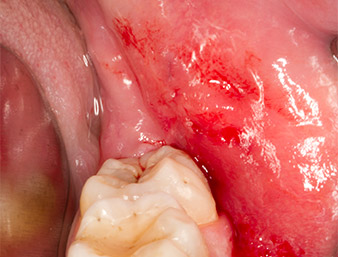

Sous bloc nerveux et anesthésie locale, le site d’intervention est ouvert et les tissus mous sont exposés afin d’accéder à la zone rétromolaire buccale (Fig. 3).

Le tissu recouvrant le reste radiculaire n’est pas entièrement ossifié et est essentiellement constitué de tissu de granulation modifié par l'inflammation (Fig. 4).